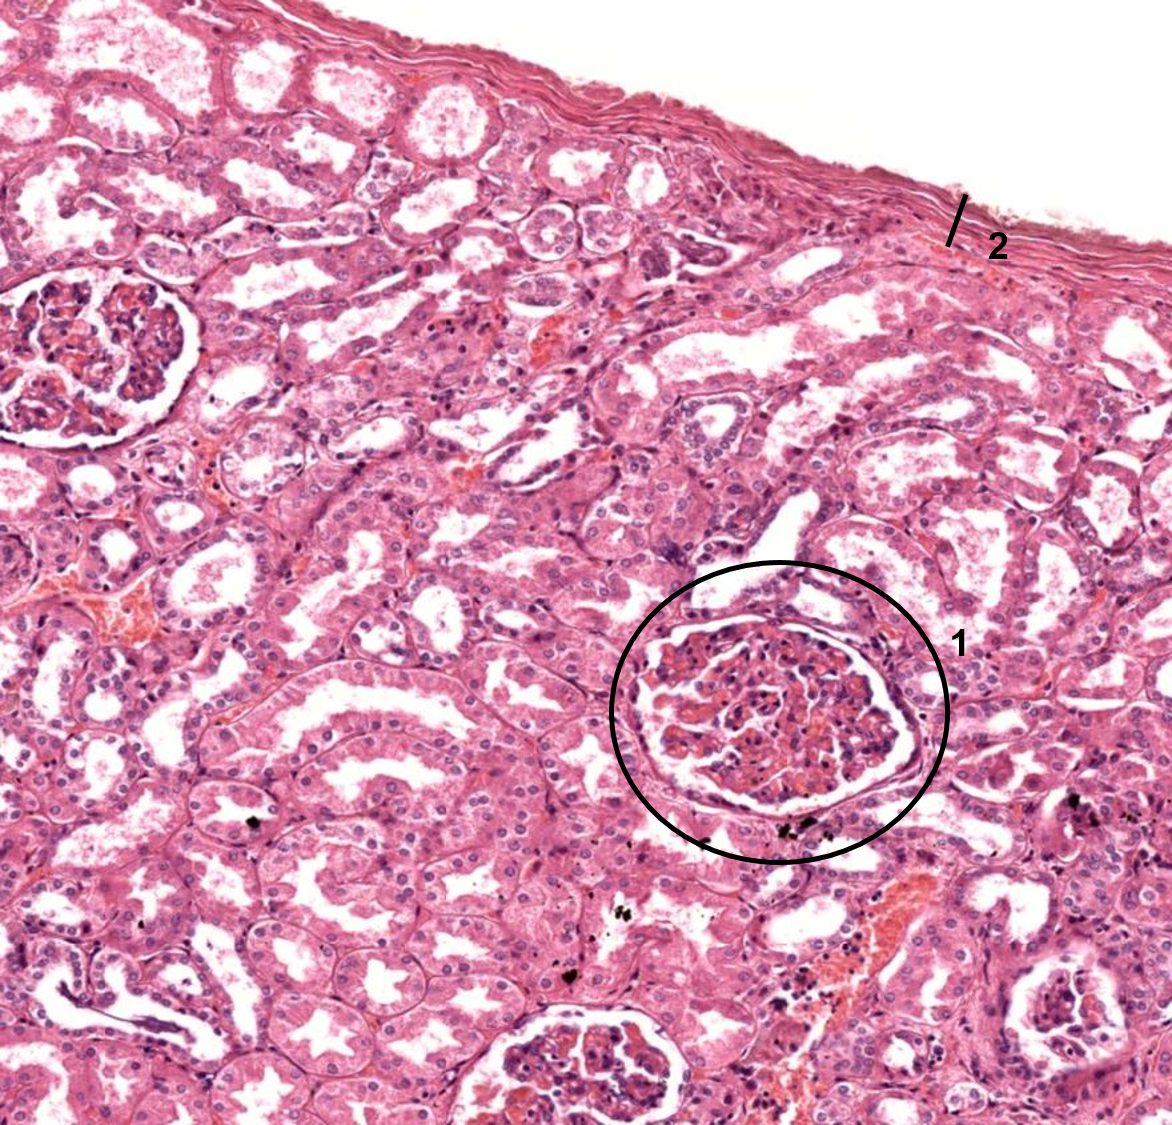

Córtex renal

Córtex renal

1: Corpúsculo renal

2: Cápsula

Córtex renal

Rim - corpúsculo renal